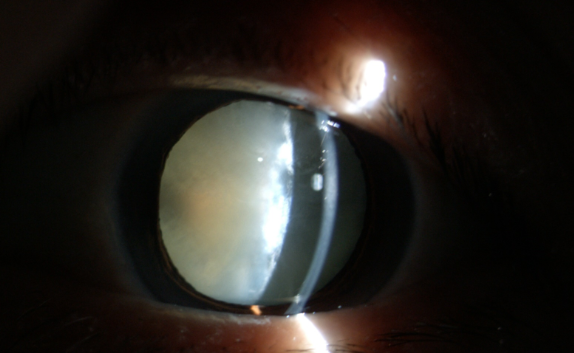

糖尿病為什么更易得白內(nèi)障

【文章導(dǎo)讀】在臨床中,很多糖尿病患者不太重視診治,尤其忽視糖尿病導(dǎo)致的多種眼科并發(fā)癥,如白內(nèi)障。糖尿病友得白內(nèi)障較普通人來(lái)說(shuō)有三個(gè)特點(diǎn):

在臨床中,很多糖尿病患者不太重視診治,尤其忽視糖尿病導(dǎo)致的多種眼科并發(fā)癥,如白內(nèi)障。糖尿病友得白內(nèi)障較普通人來(lái)說(shuō)有三個(gè)特點(diǎn):

(1)糖尿病患者比一般老年人白內(nèi)障發(fā)生率高;

(2)糖尿病患者比一般老年人白內(nèi)障發(fā)生早;

(3)糖尿病患者比一般老年人白內(nèi)障成熟快。

糖尿病合并白內(nèi)障應(yīng)盡早手術(shù)

糖尿病患者與一般的白內(nèi)障患者不同,因?yàn)樘怯褌兂?huì)伴有糖尿病性視網(wǎng)膜病變和眼部其他損害。醫(yī)生要求每3~6個(gè)月進(jìn)行一次眼科檢查,目的是延緩甚至阻斷糖尿病眼病的發(fā)生和發(fā)展。

白內(nèi)障癥狀

糖尿病患者合并白內(nèi)障盡早手術(shù)的原因:白內(nèi)障發(fā)生后,不但使患者視力產(chǎn)生障礙甚至失明,還直接影響到醫(yī)生對(duì)眼底的檢查和治療,因?yàn)闇啙岬木铙w阻斷了進(jìn)出光線。因此,糖友們的白內(nèi)障手術(shù)治療,既能解除視力障礙,還能掃除糖尿病視網(wǎng)膜病變的檢查、治療障礙,所以應(yīng)盡早手術(shù)。

手術(shù)后仍要注意控制血糖,按醫(yī)囑用藥,避免揉眼,不要做劇烈的運(yùn)動(dòng)。